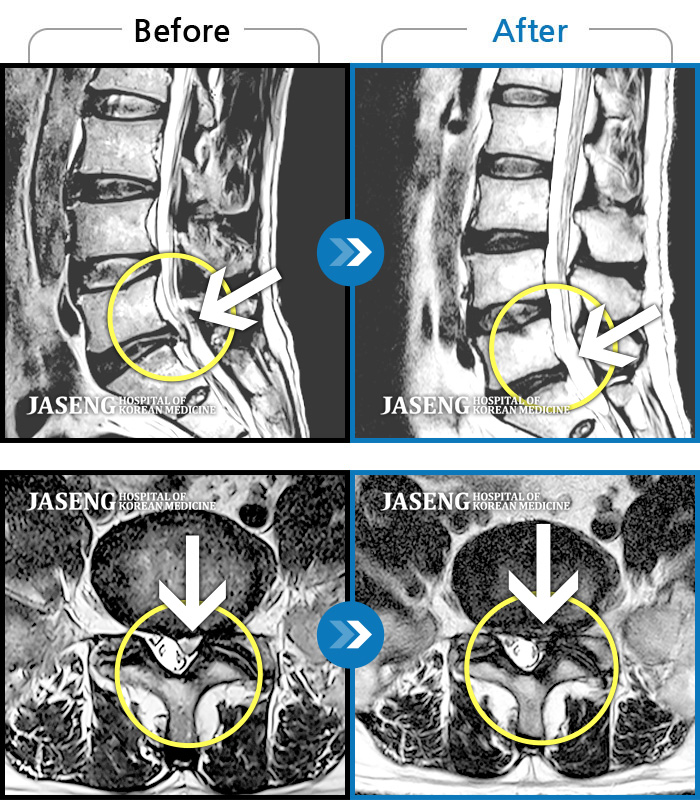

허리디스크

천안 · 김세정 원장

직업 상 무거운 물건을 많이 드는 편으로 6개월간 허리와 둔부의 통증이 지속되었으나 내원 2주 전부터 야간통증까지 동반되어 내원하였습니다.

촬영시기

2022.05.27 ~ 2024.11.02